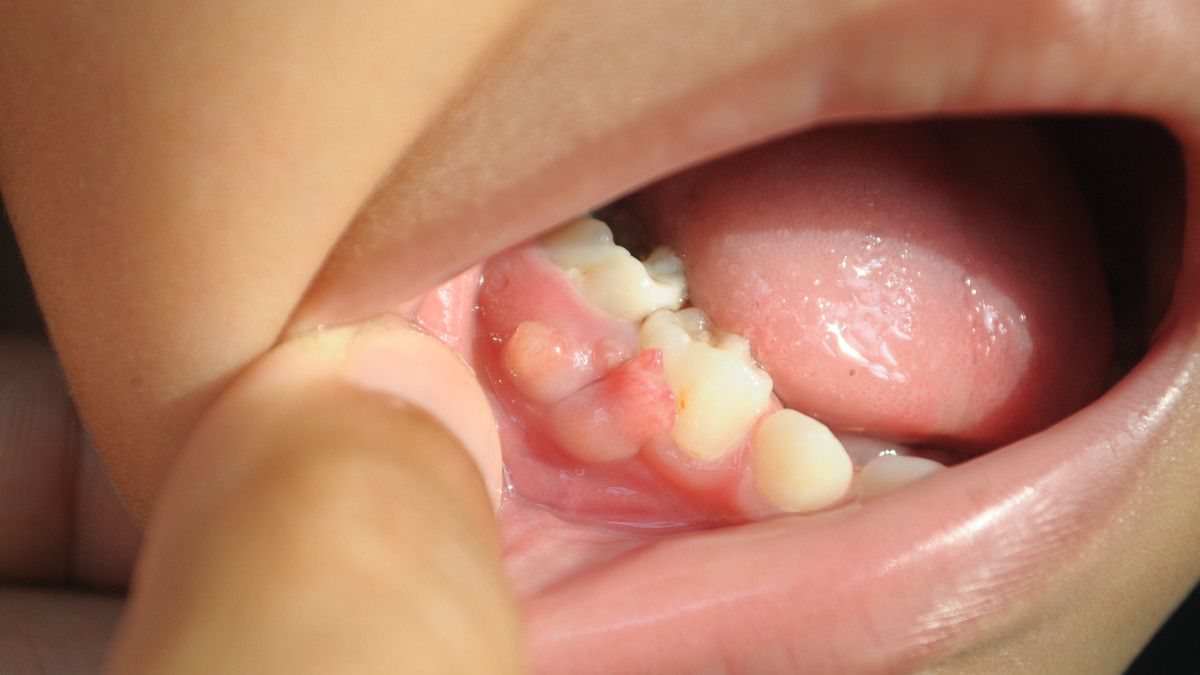

1. Gusi Membulat

Gusi melekat pada gigi dengan sudut yang landai. Jika seseorang mengalami periodontitis, gusi tampak lebih membulat dibandingkan dengan gigi lainnya.

Penting untuk kamu sadari, jika gusi yang di dekat leher gigi sudah membulat, berarti tingkat keparahan sudah meningkat.